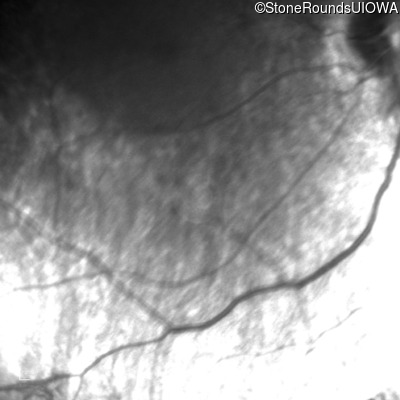

Infrared Fundus Photograph - Left - Light Perception

Exemplar